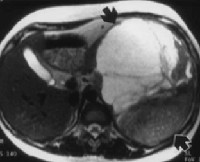

Диагноз устанавливается на основании жалоб, результатов внешнего осмотра и дополнительных исследований. Пациентов с подозрением на забрюшинную опухоль направляют на УЗИ, КТ и МРТ органов брюшной полости и забрюшинного пространства. Перечисленные диагностические методы позволяют определить структуру и локализацию новообразования, оценить степень вовлеченности близлежащих органов и выявить отдаленные метастазы в печени. Учитывая ряд признаков (форма, плотность, наличие или отсутствие капсулы, уровень гомогенности, степень васкуляризации), после проведения УЗИ, МРТ и КТ специалист может оценить злокачественность забрюшинной опухоли и выдвинуть обоснованные предположения о типе новообразования.